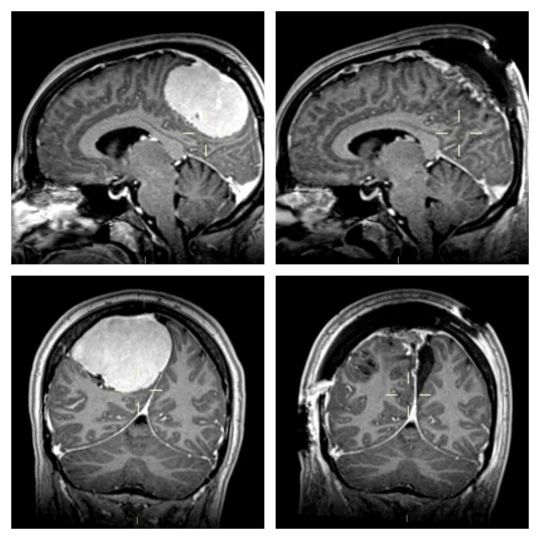

Wtedy wyszło na jaw, że Lisa ma 10-centymetrowego guza mózgu. Największego, jakiego do tej pory widzieli lokalni chirurdzy. Okazało się, że to właśnie jego nacisk na mózg powodował wszystkie dolegliwości.

Guz Lisy

Guz Lisy © Facebook

Na szczęście kolejne badania wykazały, że nie był to złośliwy nowotwó i można było go usunąć. Po guzie została tylko blizna, a migreny zniknęły. Lisa dzieli się teraz swoją historią, aby zachęcić inne osoby cierpiące na migreny do zrobienia szczegółowych badań.